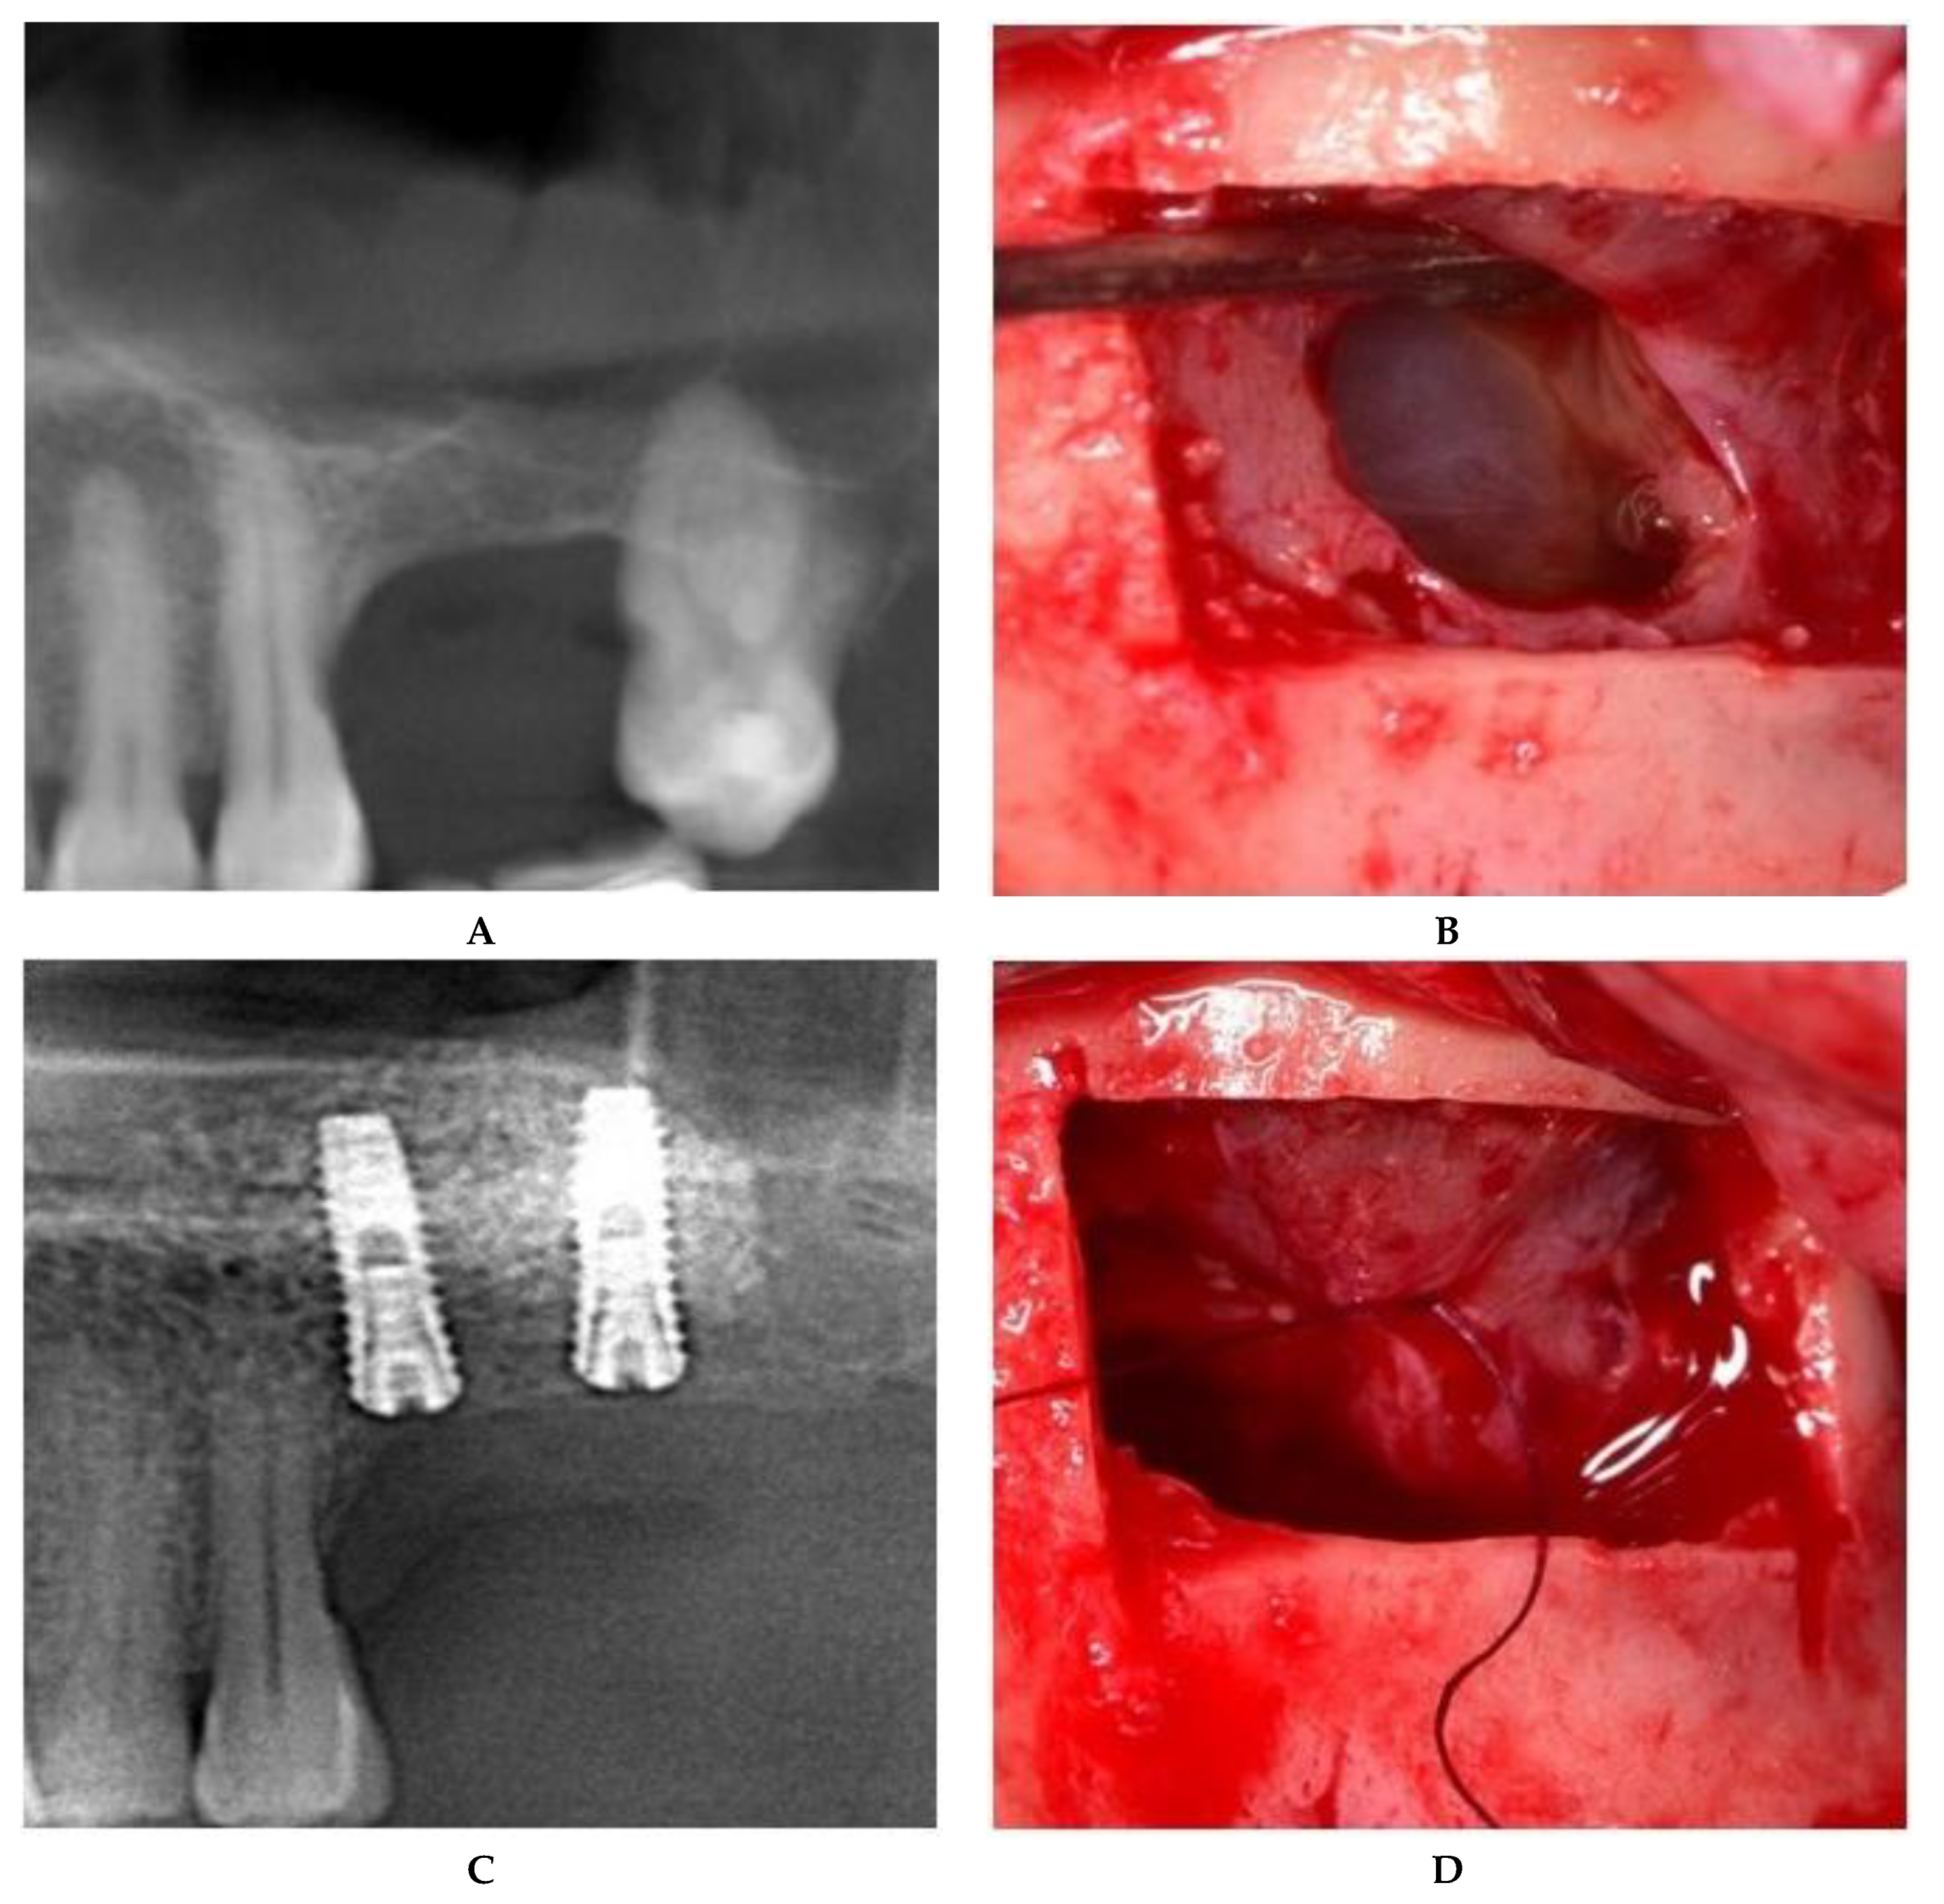

II.c. The treatment of maxillary sinus mucoceles requires deliberate incisions of the sinus membrane. The position and size of the incision were controlled by the surgeon, both to allow mucocele removal and to further seal off the Schneiderian membrane. The surgical approach to the incised Schneiderian membrane was suturing with an absorbable 6.0 suture with an 8-mm needle (SMI Company, Belgium). Fine-tipped needle holders (Devemed GmbH, Tutlingen, Germany) and anatomical tweezers were used to create three sutures, each with one double knot secured by two other simple knots (Figure 4).

Figure 4.

Sinus floor augmentation simultaneous with mucocele removal. (A) Preoperative CBCT of the left maxillary sinus. (B) Mucocele pseudocyst visible through the incision. (C) Suture of the incised Schneiderian membrane. (D) Panoramic image after implant placement.